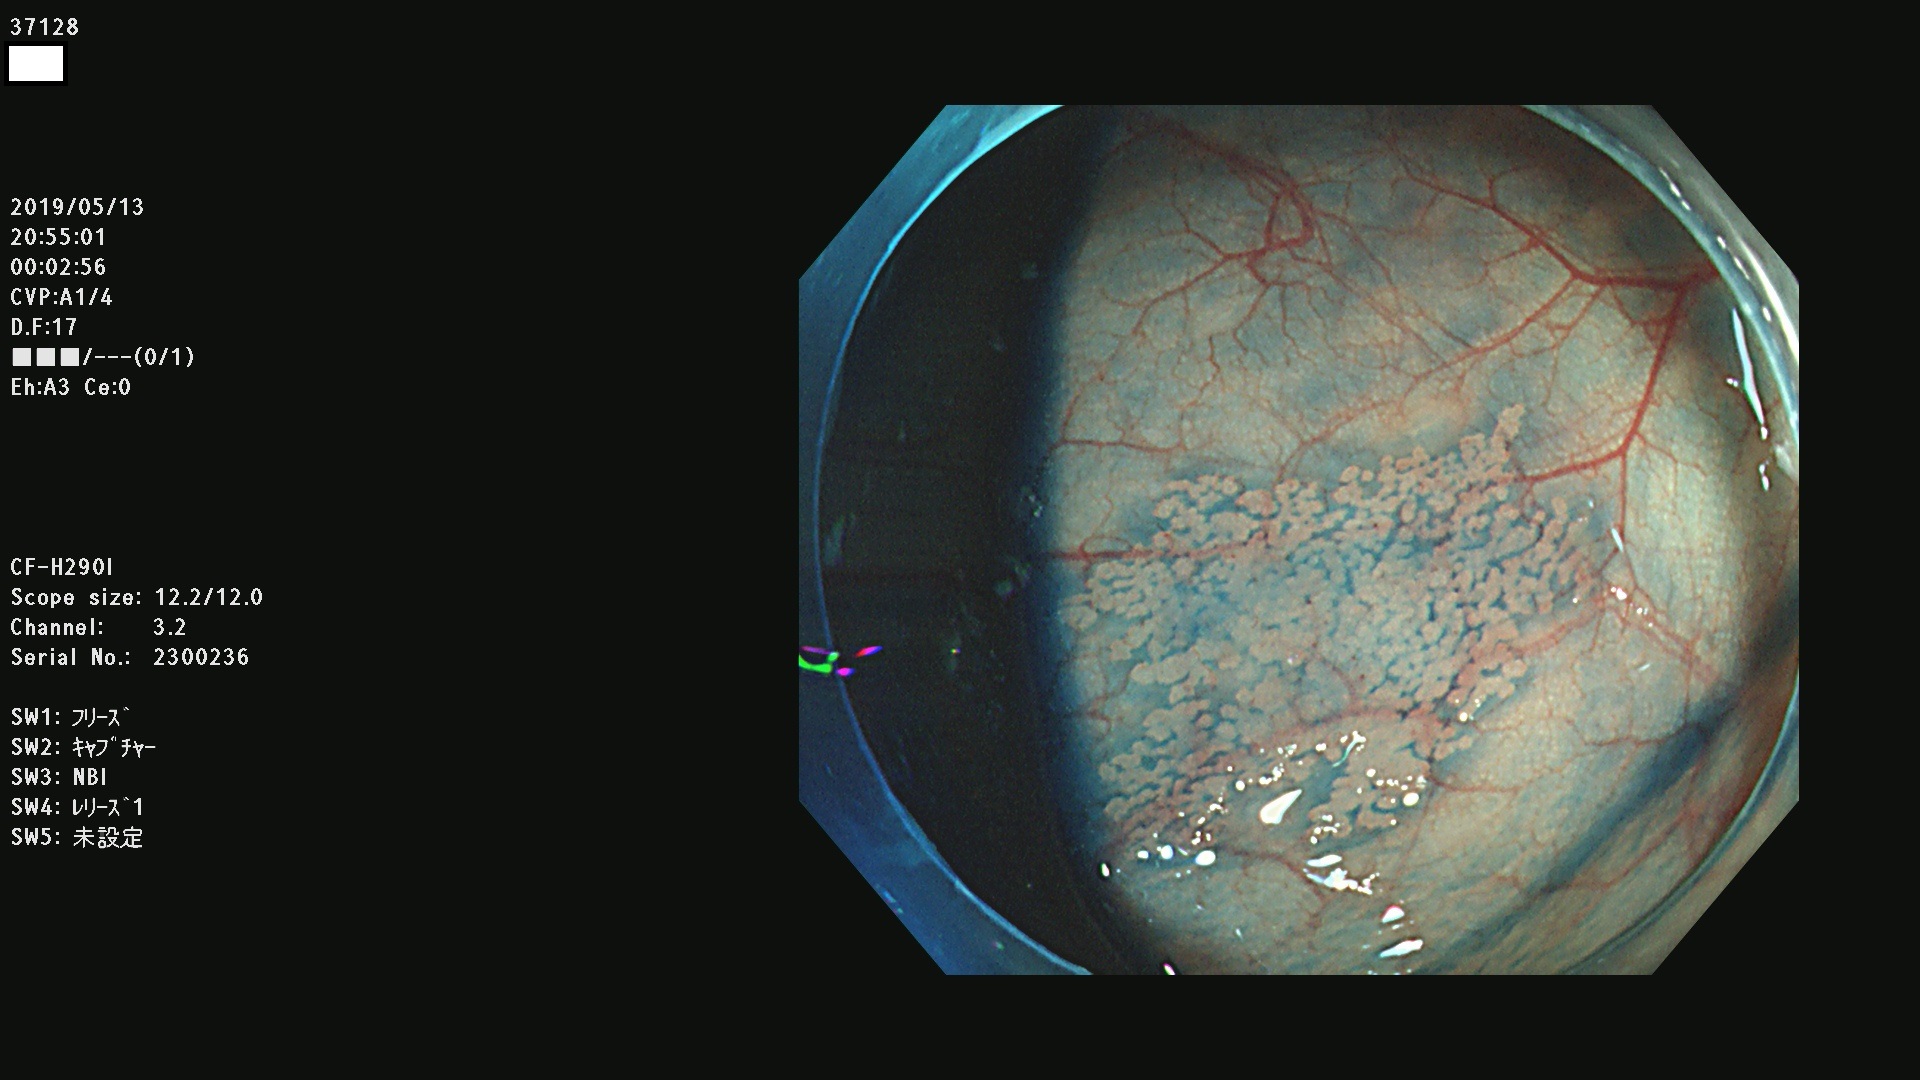

37100 37101 37102 37104 37106 37108 37110 37111 37112 37113 37115 37118(SSAPのみ) 37120 37122 37123 37124 37127(SSAPのみ) 37128(SSAPのみ) 37131 37132 37133 37134 37135 37139 37141 37142 37143 37144(SSAPのみ) 37145 37147(SSAPのみ) 37148 37149 37150 37153 37154 37157 37159 37161 37162 37163 37164 37165 37166 37167 37168 37169 37170 37171 37172 37173 37175(SSAPのみ) 37176 37177 37178 37180(SSAPのみ) 37181 37184 37185 37186 37187 37188 37189 37190 37192 37194 37197 37198

発見困難で危険性の高い平坦型病変(上記100名より抽出)